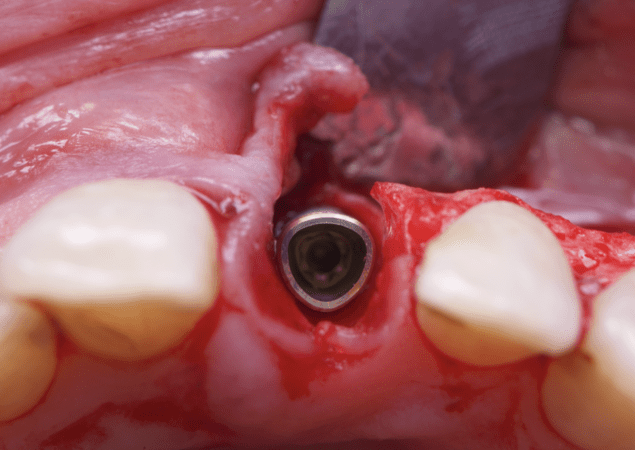

The surgical protocol began with the atraumatic extraction of tooth 1.1 to preserve as much of the alveolar socket as possible. Immediately following extraction, an N1 implant was placed into the socket using a guided surgical approach to ensure ideal three-dimensional positioning. The “one abutment one time” technique was applied to minimize soft tissue manipulation during the healing phase, which is particularly important in esthetic areas.

Given the significant buccal defect, guided bone regeneration (GBR) was performed simultaneously. A mixture of autologous bone and creos™ xenogain™ was applied to the defect and covered with a resorbable creos™ membrane to restore ridge width and support the buccal contour. In addition, a connective tissue graft was harvested and placed in the vestibular region to increase the thickness of keratinized mucosa. This combined approach addressed both hard and soft tissue deficiencies, providing the biological foundation for a stable and esthetic outcome.